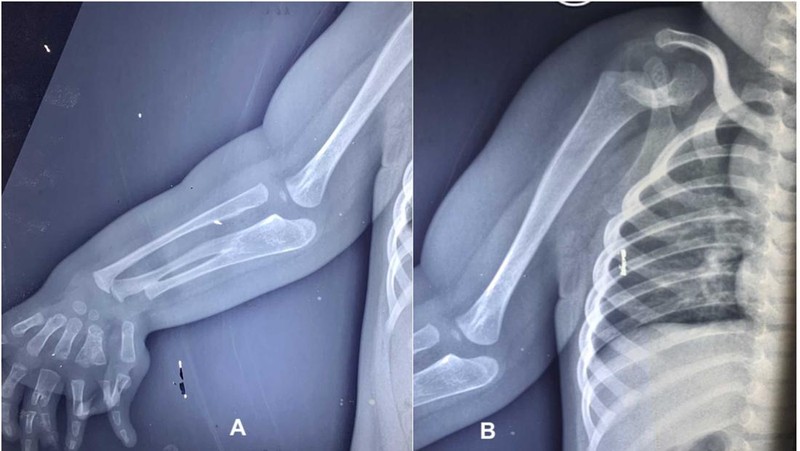

Berdasarkan hasil pemeriksaan, terlihat adanya pengecilan otot yang nyata di sekitar bahu dan skapula, disertai tidak adanya gerakan aktif pada abduksi, fleksi, maupun rotasi bahu. Siku dalam posisi fleksi 30 derajat tanpa kemampuan melakukan supinasi maupun pronasi. Lengan bawah dan pergelangan tangan tampak melebar.

Berdasarkan hasil pemeriksaan, terlihat adanya pengecilan otot yang nyata di sekitar bahu dan skapula, disertai tidak adanya gerakan aktif pada abduksi, fleksi, maupun rotasi bahu. Siku dalam posisi fleksi 30 derajat tanpa kemampuan melakukan supinasi maupun pronasi. Lengan bawah dan pergelangan tangan tampak melebar.Foto: jurnal PlumX Metrics

Selain itu, rontgen tangan menunjukkan duplikasi tipe III pada jari tengah, duplikasi tipe V pada jari manis, jari kelingking yang mengalami deviasi ulnar, serta pergelangan tangan dengan tiga tulang. Sementara itu, anggota gerak atas kiri, wajah, tulang belakang, panggul, dan ekstremitas bawah tampak normal. Pasien tidak mengalami obesitas, dan hasil parameter darah berada dalam batas normal.Foto: jurnal PlumX Metrics